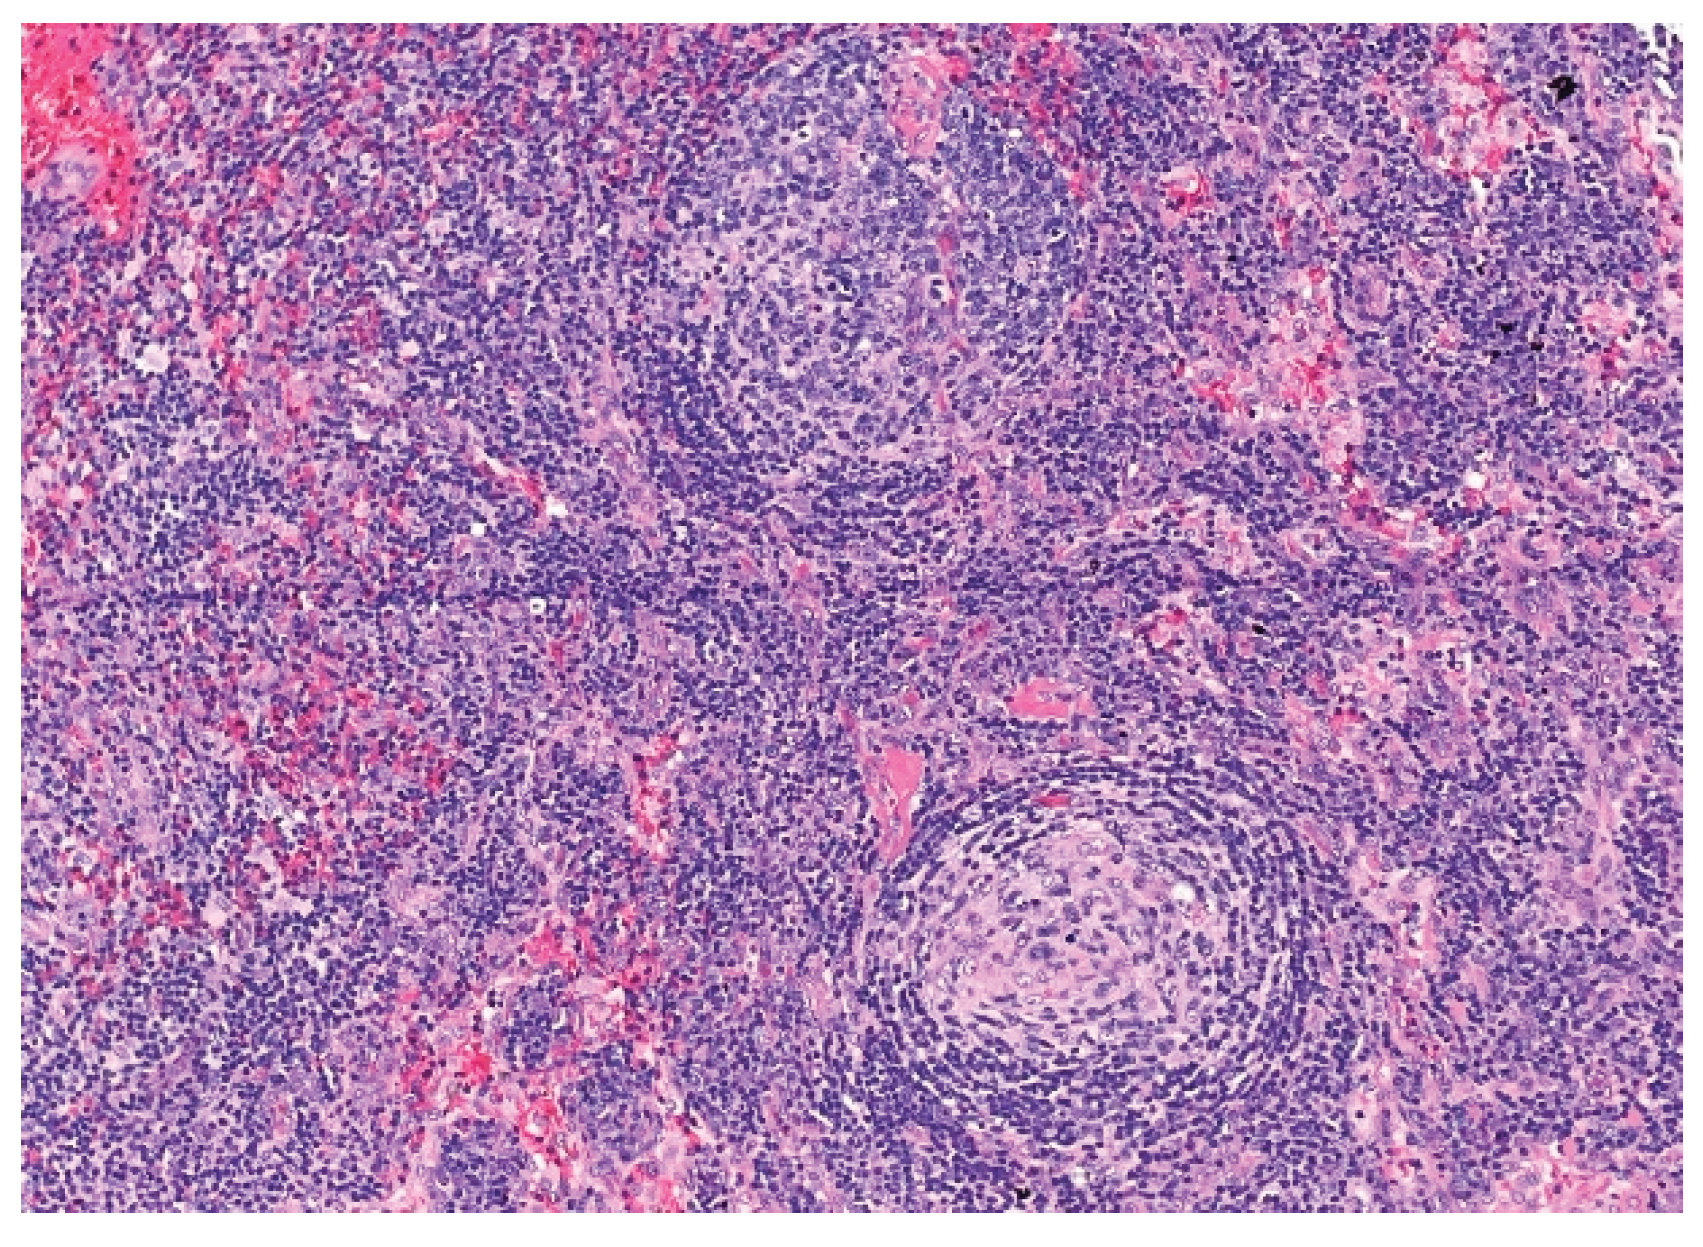

Over the following weeks, the patient developed ascites and worsening constitutional symptoms. Excisional biopsy of a lymph node was subsequently performed and demonstrated HHV-8-positive MCD, confirmed by immunohistochemical staining for LANA-1, showing scattered nuclear positivity in lymphoid cells (Figure 1). Histology also revealed characteristic "onion-skinning" of mantle zone lymphocytes (Figure 2) and regressed germinal centers with increased interfollicular vascularity and hyalinization (Figure 3), findings consistent with HHV-8–associated MCD. Rituximab monotherapy was initiated, resulting in clinical improvement, resolution of constitutional symptoms, and stabilization of ascites.

Figure 2. Higher-power view of secondary follicle showing characteristic "onion-skinning" of mantle zone lymphocytes. (H&E, 20x). This histopathologic feature can be seen in all types of Castleman disease. The concentric layering of small lymphocytes around atrophic germinal centers resembles an “onion-skin” pattern.